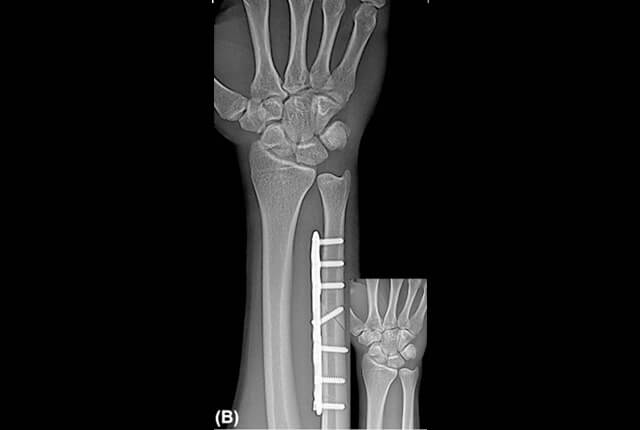

画像検査

• 単純X線でplus variance

• 単純X線でDRUJの開大

単純X線でDRUJの開大

尺骨短縮術

plus varianceでDRUJ不安定性がない症例に行います。